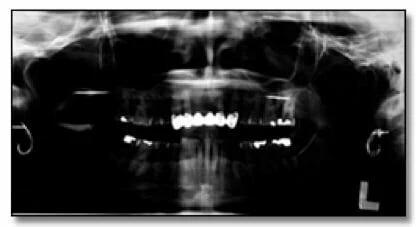

Hình 34b: Hinh ảnh bị phơi sáng quá mức (Liều bức xạ cao)

Hai hình ảnh trên cho thấy việc chụp với liều tia quá cao có thể dẫn đến các thất bại trong việc phát hiện các đặc điểm bệnh lý.

Hình ảnh thể hiện mức độ tiếp xúc quá mức có thể dẫn đến việc không phát hiện được các đặc điểm bệnh lý. Hình 34a là phiên bản nâng cao kỹ thuật số của bức ảnh 34b. Có thể thấy Hình 34b bị phơi sáng quá mức khi chụp, thể hiện rõ ràng sự xuất hiện của một vùng bức xạ gây ra sự mở rộng và mỏng đi của phần xương bên dưới của hàm phải – những đặc điểm không thể hiện rõ trên bản gốc.